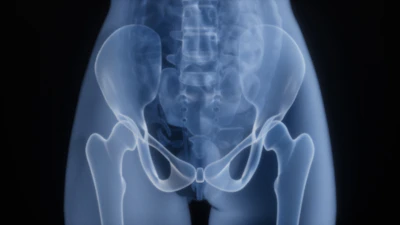

Pelvic Floor Therapy

Your pelvic floor has muscles too. We treat disorders of the pelvic floor including post-partum care (vaginal or C-section), incontinence, constipation, pelvic pain. prolapse, etc.